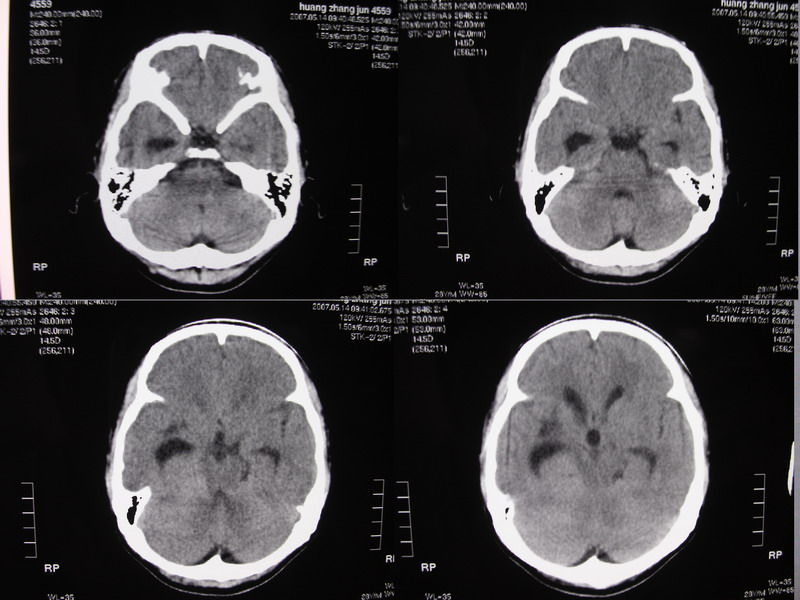

以下是引用余辉在2007-5-14 17:03:00的发言:[br]右侧脑室颞极后方可见高密度块状影,颞极呈杯口状推挤前移,右侧大脑脚及丘脑上部受推挤向对侧移位,右丘脑区结构紊乱,增强扫描病灶有不规则强化,以下部颞极后方为著。胼胝体压部及右枕叶视辐射区低密度改变,右基底节区低密度改变,双侧脑室不对称积水征象,意见:1颞极后方—右丘脑区占位性病变,如室管膜瘤等2脑血管疾病如moyamoya,局部脑血管畸形等3脑膜炎等后遗改变,建议mr及脑血管造影检查[br][br][本贴已被 余辉 于 2007-5-14 17:05:26 修改过]

以下是引用千里草在2007-5-14 15:54:00的发言:[br]考虑:1、双侧梗阻性脑积水;[br] 2、右侧基底节区缺血性脑血管疾病。

以下是引用ssmmxx在2007-5-14 18:05:00的发言:[br]颞极后方—右丘脑区占位性病变,如室管膜瘤等2脑血管疾病如moyamoya,局部脑血管畸形等

以下是引用qiuleiyu在2007-5-14 18:43:00的发言:[br]支持;1,交通性脑积水(病脑后遗征?)2,右基底节及胼骶体压部低密度灶伴轻度占位表现,结合年龄考虑moyamoya,建议dsa.[br]